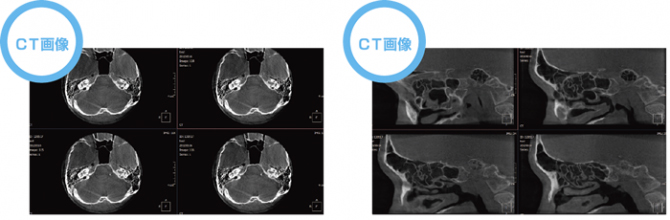

KR-X scan

当院では高性能な耳鼻科用CTを導入しました。

3種類の断面に該当する、それぞれの軸を移動させることにより、求める位置の断面が確認でき、また軸の回転機能を利用すると、座標軸に対し垂直ではない方向の断面も確認することができます。

セファロ撮影時間は1秒と短時間、かつ小児患者様の鼻の根元の薄い骨もきちんと映るため、小児患者様へのご使用に最適です。 また、2種類の画像フィルタを使い分けることで、軟組織と硬組織の両方を鮮明に撮影することができます。